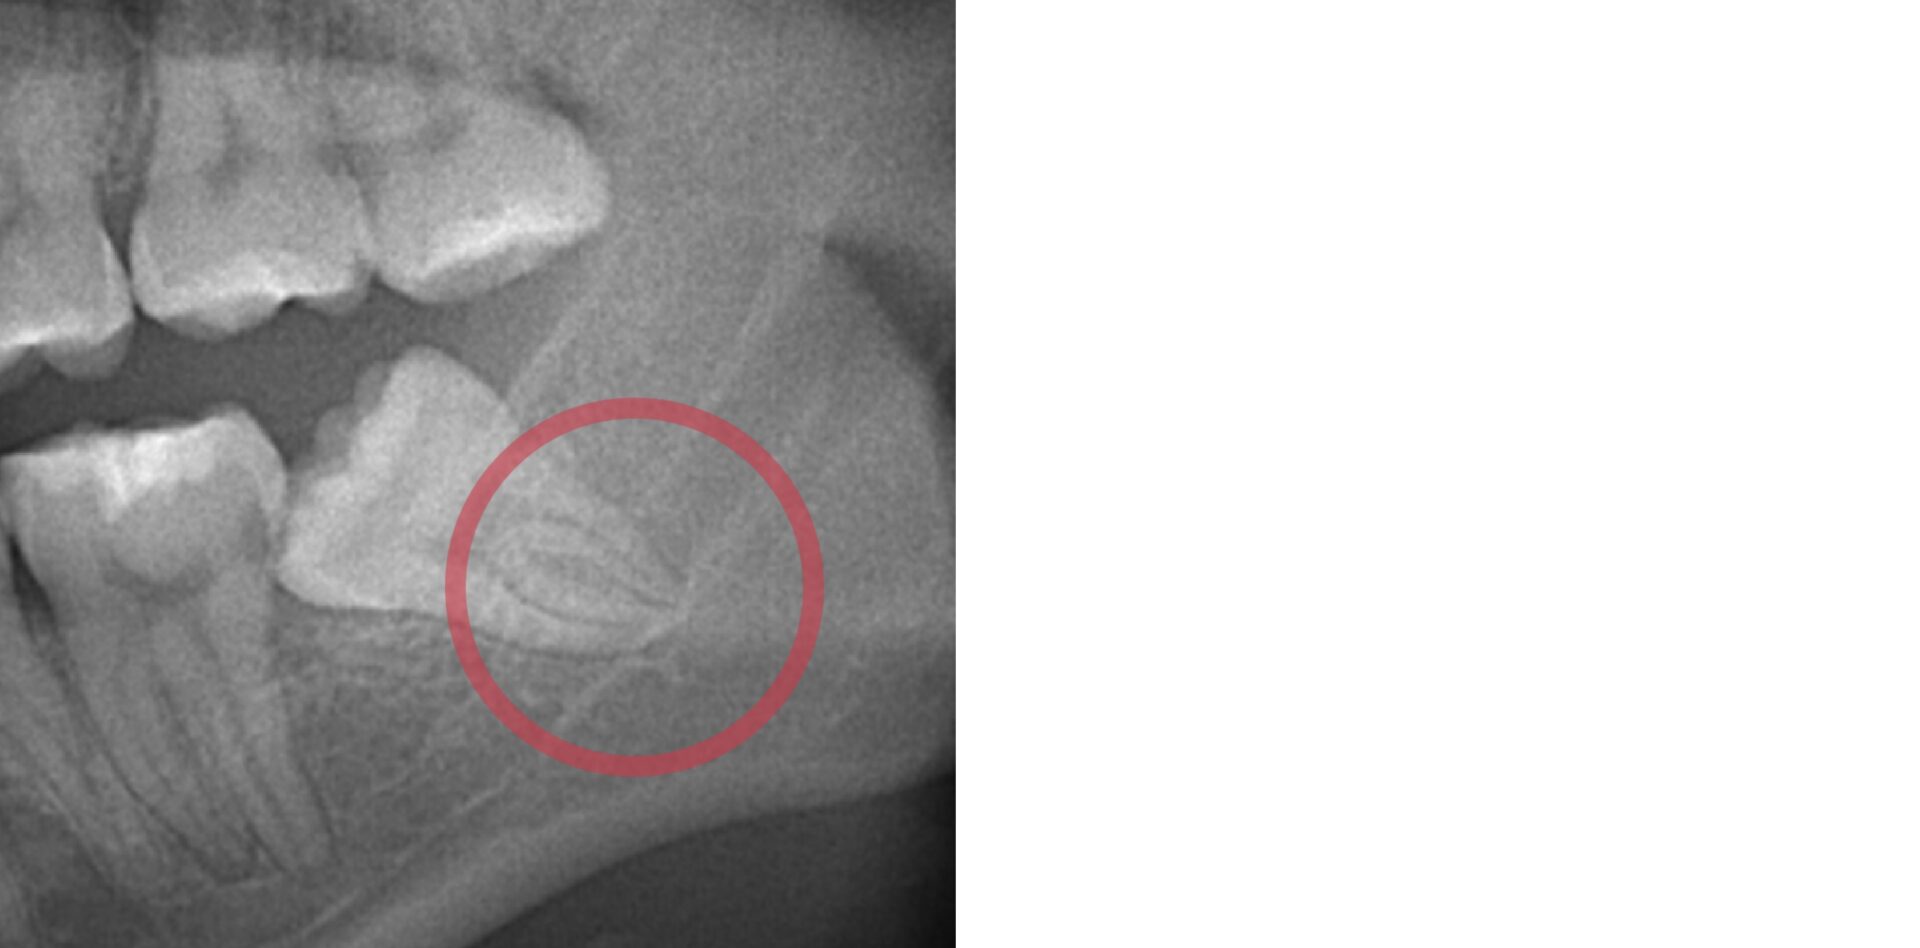

- 下顎入ってる